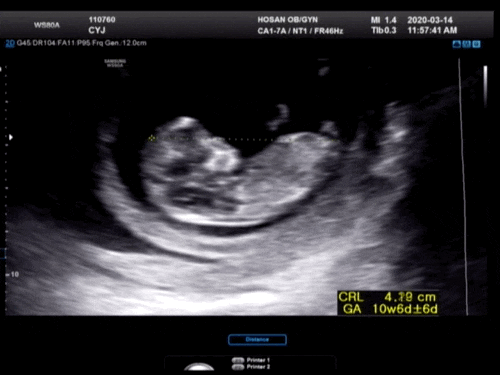

일단 1차 기형아 검사 초음파에서 제일 먼저 확인한 머리~꼬리뼈 길이www #임신 12주차 정도가 되면 6~7cm 정도 된다고 합니다. ^^

1차 기형아 검사 중에 #12주 성별도 한번 봐주셨는데 다리 사이에 뭔가 삐걱거리는 게 존재감이 가득하죠?그래서 혹시 아들이에요? 그러면 탯줄일 수도 있고 손일 수도 있고 저게 없어질 수도 있다고 ㅋㅋㅋ 16주 지나서 보는 게 제일 정확하다고 했어요! 아들이든 딸이든 건강했으면 좋겠어요^^!

심장 박동도 확인해 주세요.153비트가 나왔는데 정상이래요(웃음)